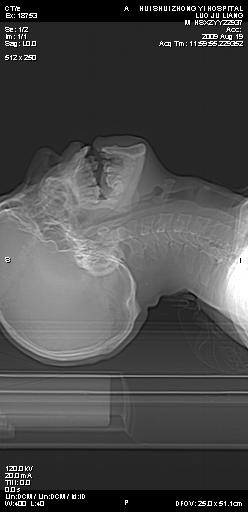

标题: CT21693:男 58岁 右侧咽部疼她2天余 PE:右侧扁桃体肿大 压痛 [打印本页]

标题: CT21693:男 58岁 右侧咽部疼她2天余 PE:右侧扁桃体肿大 压痛

1 弥漫性肿胀,与周围组织分界清晰,发病急,有明显症状,考虑急性炎症【wbc]

右化脓性扁桃体炎症伴咽后壁脓肿形成.